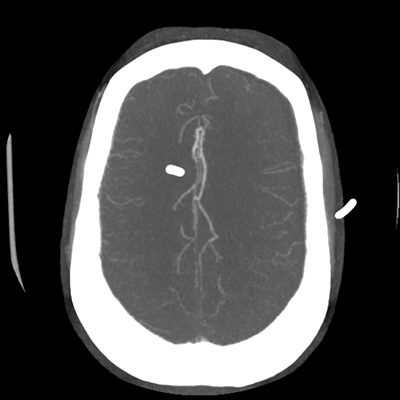

Starting with the non-contrast head CT, we can appreciate that there's actually not much residual subarachnoid blood at all; it's essentially all resorbed already (and cleared through the EVD). The ventricular caliber is stable. With the CTA head (for convenience's sake, the MIPs were shown), it's subtle, but we can see that the PCAs on each side are not as smooth and regular. The right MCA, starting at the bifurcation, also becomes narrower. This is [radiographic] vasospasm. Now, looking at the CT perfusion-- specifically, the Tmax (MTT) map that were selected-- there's clearly some abnormality within the bilateral cerebellar hemispheres and occipital lobes. Not a lot, but it's there. Delving further into this map, we can appreciate that the areas of abnormality are mainly green, signifying that these areas have Tmax > 6 seconds. This is the threshold that is specific, not sensitive, for vasospasm.

Putting this all together, we have thus identified radiographic vasospasm with the vessel imaging, with perfusion abnormalities that are concordant with it. Does the area of vasospasm and hypoperfusion correlate with the patient's clinical exam?